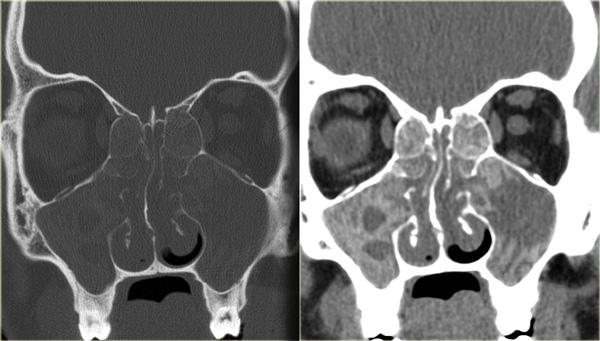

Hình ảnh bên trái của một bệnh nhân bị viêm xoang cấp tính và bệnh lý tế bào khí sàng.

Bệnh nhân nhập viện với triệu chứng nhìn mờ.

Hãy quan sát kỹ các hình ảnh trước, sau đó tiếp tục đọc.

Chú ý dịch trong mỏm yên trước trái.

Dây thần kinh thị giác chạy ở phía trong của nó.

Tiếp tục xem các hình ảnh mặt phẳng coronal.

Chuỗi xung T2W mặt phẳng coronal cho thấy sự giãn rộng của mỏm yên.

Chuỗi xung T1W cho thấy mất tín hiệu mỡ bình thường so với bên phải, và lan rộng vào đỉnh hốc mắt (mũi tên đỏ).

Đây là nang nhầy của mỏm yên trước với tổn thương thứ phát dây thần kinh thị giác.